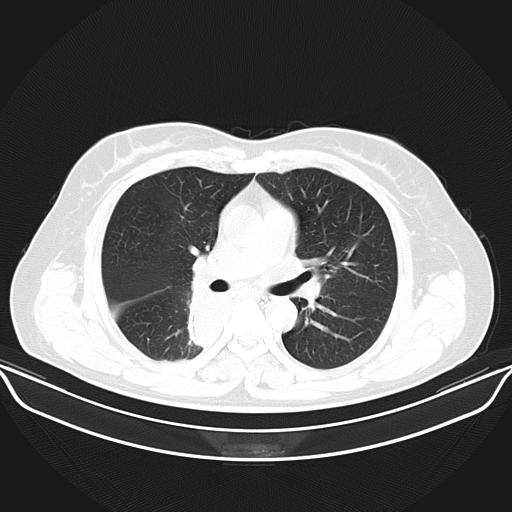

标题: CT22224:肺部肿块

f,48,主因咳嗽咳血来我院检查,无发热。

1)右肺下叶背段团块状软组织密度影;建议抗炎治疗后复查排除肿瘤性病变。2)右侧少量胸腔积液。

谈一谈个人的看法:机器性能应该不错,可惜扫描方法不太正确,即没有及时薄层扫描图像,也没有增强检查,这样的检查方法不正确的图片拿来研究只能是猜一猜:右肺下叶阻塞性改变,建议进一步检查删除肺癌。

支气管镜检查未见异性细胞,抗炎治疗20天,肿块明显缩小。